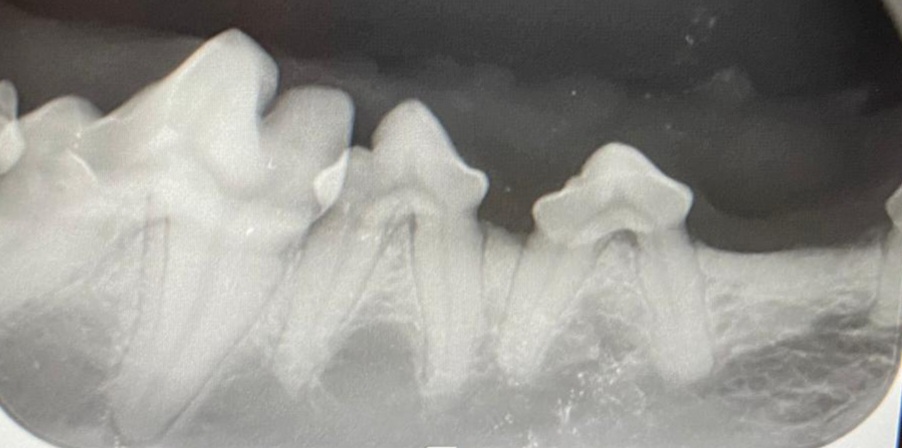

- das Dentalröntgen zur Abklärung dieser Patienten

Die Voraussetzung für eine gute Therapie dieser Tiere, ist eine gute und genaue Diagnostik. Hierfür kann man auf das intraorale Dentalröntgen nicht verzichten. Die meisten krankhaften Veränderungen befinden sich im äußerlich nicht sichtbaren Bereich der Zahnwurzel und des Zahnhalses und können nur durch bildgebende Verfahren sichtbar gemacht werden.